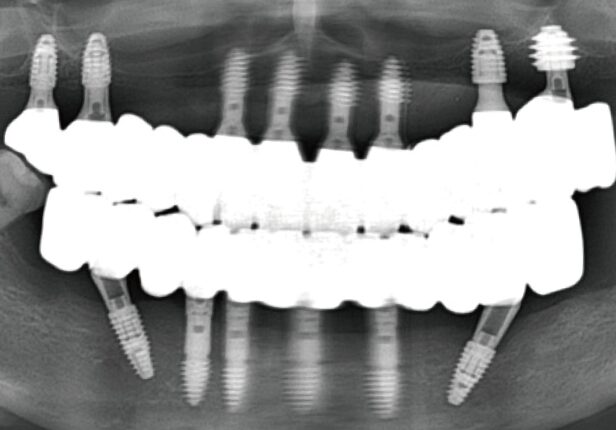

Pre-surgery panorama

Post-surgery panorama

Final Crown Panorama